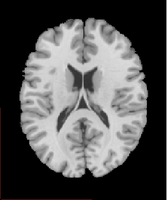

Les images IRMsujet1211anat avec et Sans Scalp sont issues des images d’IRM anatomique. Pour le même sujet, on peut visualiser l’image anatomique correspond au cerveau avec l’enveloppe crânienne ou, si on lui applique un traitement qui utilise un masque, au cerveau seul (Sans scalp)

Ces images anatomiques de bonne qualité permettent de se localiser dans les différents plans de coupe et de repérer les grandes régions cérébrales (lobe occipital, temporal, frontal; pariétal) ainsi que les principales structures cérébrales (Hémisphères, cervelet, cortex cérébral, substance grise, substance blanche, corps calleux, hippocampe…). L’image sans scalp propose un rendu de surface des hémisphères cérébraux et permet de repérer les grandes circonvolutions.

| Image anatomique sans scalp, coupe axiale | Image anatomique avec scalp, coupe axiale. Un calque colorisé montrant les aires de Brodmann est superposé à l'image. |